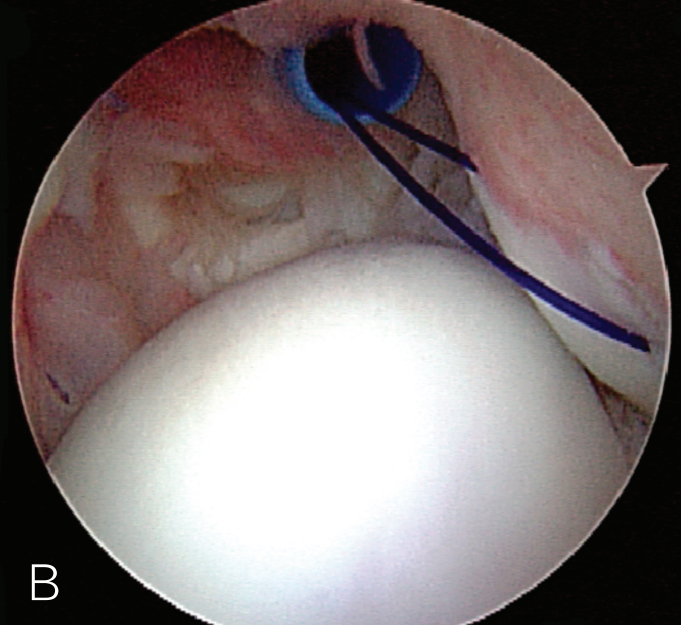

B. 应首先用腰椎穿刺针确定辅助入路的恰当位置和方向。然后在皮肤上做一个小切 A B 口,钻头导向器置入关节。